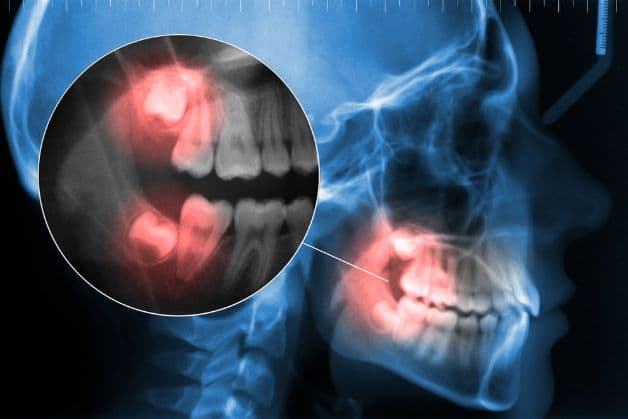

– Nhổ bỏ răng khôn mọc lệch, mọc ngầm: răng số 8 là răng hàm lớn, không có nhiều tác dụng trong ăn nhai, dễ mọc lệch. Nhiều trường hợp răng mọc thẳng, không gây ra bất cứ cản trở nào. Nhưng trong trường hợp răng mọc lệch, ngầm, đâm vào răng bên cạnh thì cần được nhổ bỏ. Điều này giúp bảo tồn tối đa các răng khác. Hiện nay có phương pháp nhổ răng khôn bằng máy Piezotome hạn chế chảy máu và đau nhức cho bệnh nhân.

Tuy nhiên, khác với các răng ở vị trí bên ngoài dễ thấy, răng hàm nằm ở vị trí sâu nhất nên việc nhổ răng hàm cũng đòi hỏi những yêu cầu khắt khe hơn. Để đảm bảo an toàn khi nhổ răng hàm, đòi hỏi sự khéo léo và chuyên môn cao của các bác sĩ thực hiện. Cần biết răng hàm có thể có tới 4 chân, một số răng có chân cong và có xu hướng xoắn, việc nhổ bỏ những răng này đặc biệt khó khăn hơn. Răng số 8 mọc lệch, mọc ngầm cũng là 1 trường hợp đặc biệt cần lưu ý khi tiến hành nhổ răng hàm.